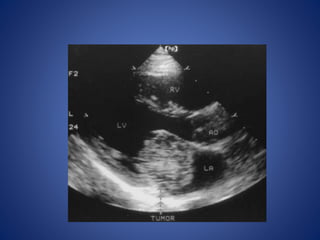

Cardiac diseases

• Cardiac disorders are the most common cause of ischemic stroke

in children and account for up to 50% of strokes.

• The risk of stroke in children with congenital heart disease is

related to the abnormality, diagnostic and surgical procedures,

and associated genetic or acquired factors that predispose

children to thrombosis.

• Cardiac disorders can lead to the development of intracardiac

thrombi that may embolize to the brain or can lead to

thrombosis in cyanotic patients with anemia